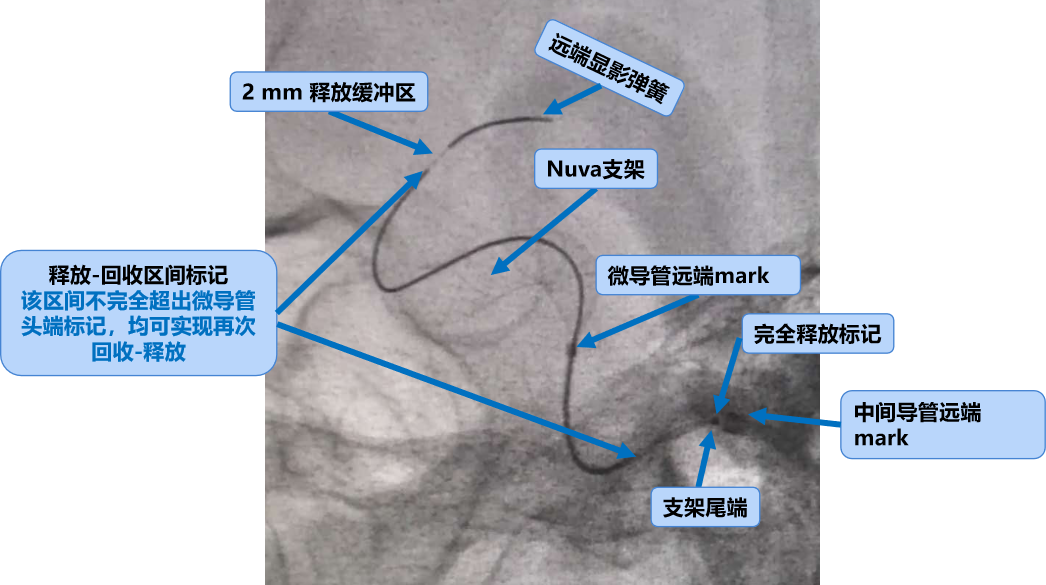

释放开始头端无需完全贴壁,支架一般在定位显影导丝以内2mm;还需预留2mm后期回缩!

Nuva®释放的关键是保证张力的释放和平衡,以实现装置顺利打开并与血管完美贴壁。

再次强调,由于 Nuva®具有优异的柔顺性,为了确保Nuva®有足够的锚定强度,锚定区长度应超出瘤颈远端至少10~15 mm。

当输送导丝上的释放显影区间标记末端到达微导管远端标记时,Nuva®已经到达可回收的极限位置,即超出微导管远端标记时,Nuva®将不可再进行回收。

释放进入尾部释放阶段,该阶段在微导管中的长度约5mm~8mm;当输送导丝完全释放标记超出微导管远端标记时,Nuva®完全释放。